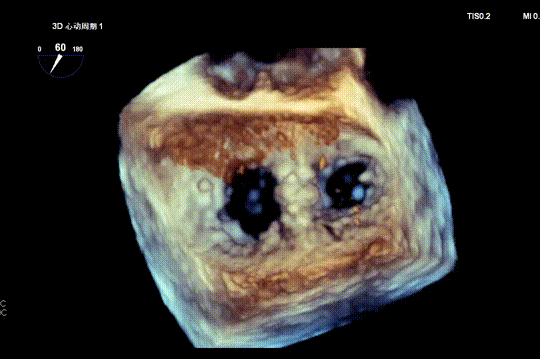

3D color Doppler

Mitral valve Zone 2

Color Doppler of Mitral valve Zone 2